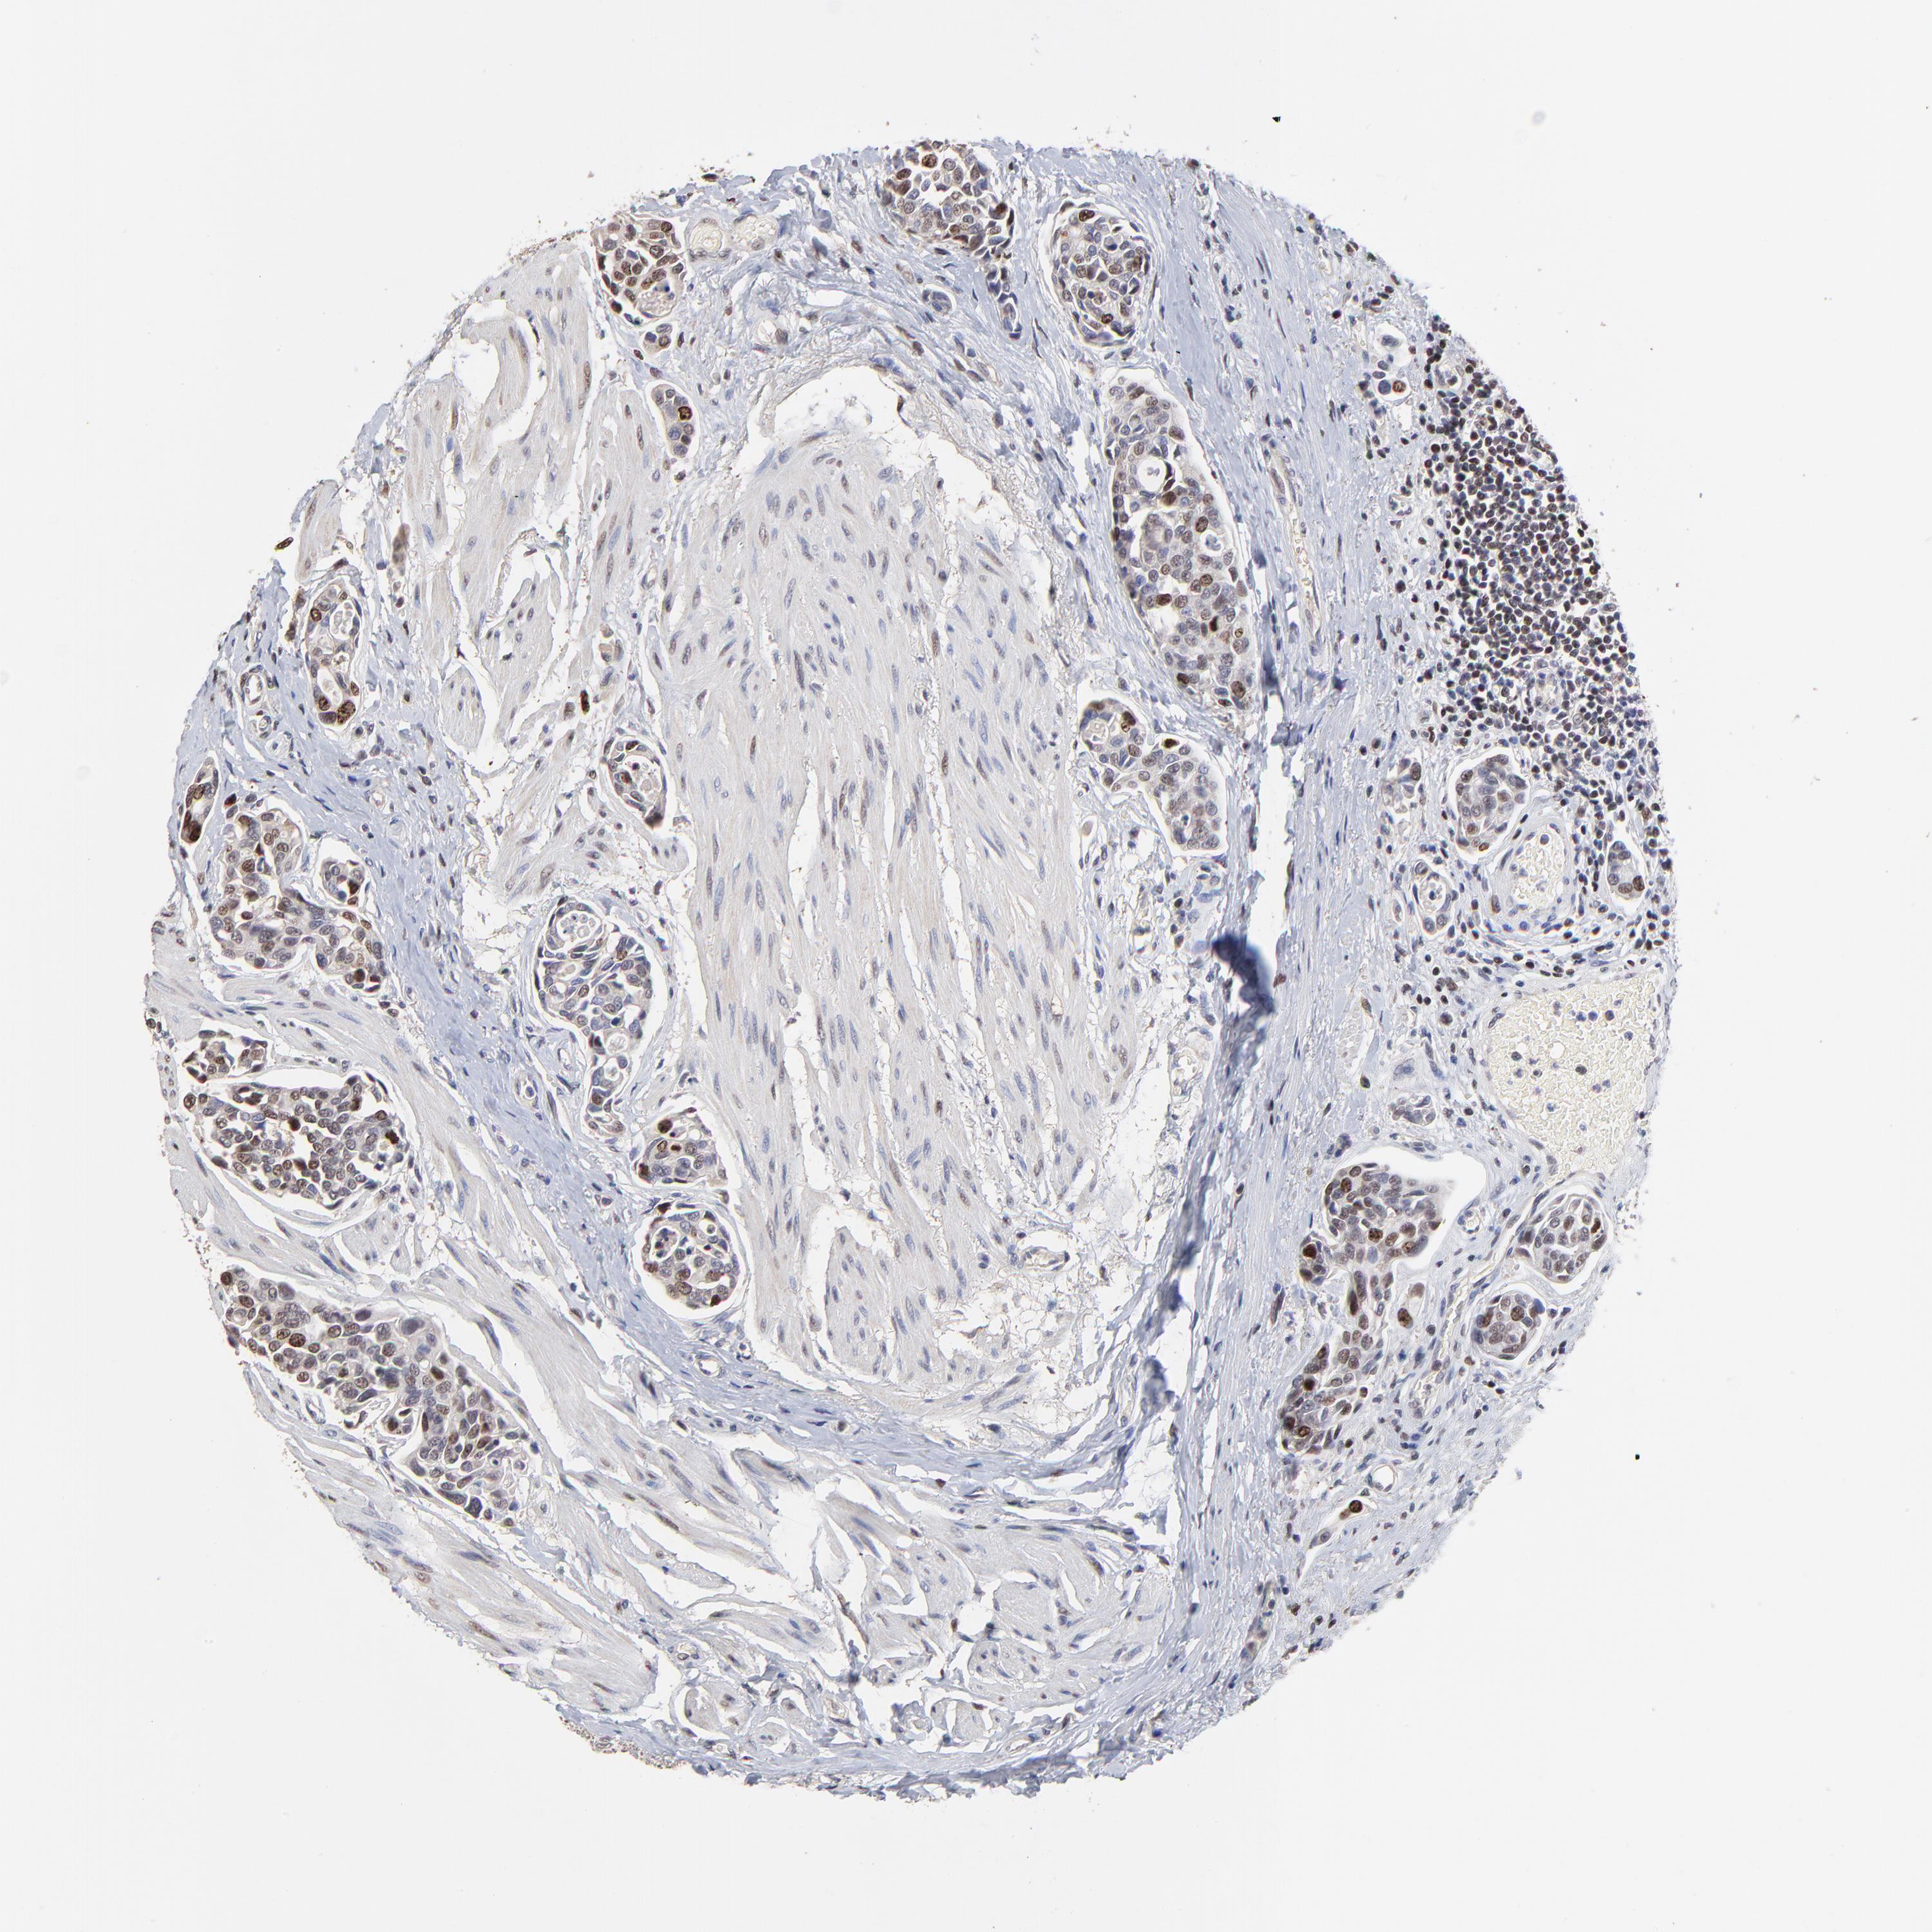

UROTHELIAL CANCER - Protein expressioni

A mouse-over function shows sample information and annotation data. Click on an image to view it in a full screen mode. Samples can be filtered based on level of antibody staining by selecting one or several of the following categories: high, medium, low and not detected. The assay and annotation is described here.

Note that samples used for immunohistochemistry by the Human Protein Atlas do not correspond to samples in the TCGA dataset.

Antibody stainingi

Antibody staining in the annotated cell types in the current human tissue is reported as not detected, low, medium, or high, based on conventional immunohistochemistry profiling in selected tissues. This score is based on the combination of the staining intensity and fraction of stained cells.

Each image is clickable and will lead to virtual microscopy that enables deeper exploration of all samples and also displays staining intensity scores, fraction scores and subcellular localization as well as patient and tissue information for each sample.

Antibody HPA002830

Antibody CAB004270

Staining

High

Medium

Low

Not detected

Intensity

Strong

Moderate

Weak

Negative

Quantity

>75%

75%-25%

<25%

None

Location

Nuclear

Cytoplasmic/membranous

Cytoplasmic/membranous,nuclear

Urothelial carcinoma, High grade

Urothelial carcinoma, Low grade